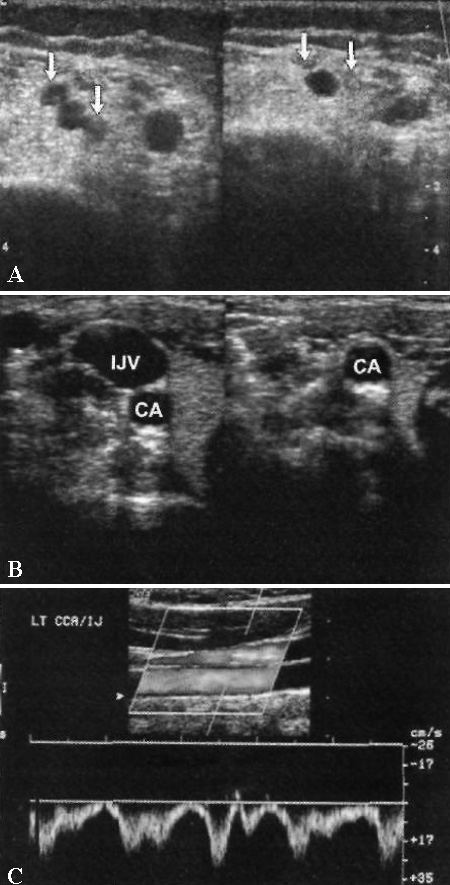

Наиболее специфичным ультразвуковым признаком тромбоза глубоких вен верхних конечностей является утрата полной сжимаемости сосуда. Следующим по специфичности методом УЗИ ТГВ является цветовая допплерография. Быстрый вдох обычно вызывает спадение внутренней яремной и подключичной вен. Отсутствие этого признака, нарушение подвижности стенки сосуда или отсутствие изменения скорости кровотока могут быть признаками наличия обструктивного тромба. Пульсовая допплерография позволяет обнаружить нарушения кровотока, характеризующееся уменьшением сердечной пульсации и дыхательной периодичности, а также выявить отсутствие кровотока (фото 10, фото 11).

Фото 10. Вены верхней конечности. А – поперечное ультразвуковое изображение нормальной вены верхней конечности. В – поперечное изображение внутренней яремной вены. С – цветовая допплерограмма нормальной внутренней яремной вены и сонной артерии, локализованной кзади. Наблюдается полное заполнение цветом вено с нормальной дыхательной периодичностью кровотока. IJV – внутренняя яремная вена; CA – сонная артерия